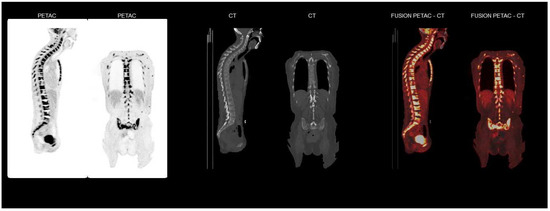

Basal cell carcinoma (BCC) is the most common cancer in Caucasians. It is slow growing and rarely metastasizes. If left untreated over time, invasive growth can occur. We present a patient case with a primary BCC located in the right sub-mammary area, with [...] Read more.

Basal cell carcinoma (BCC) is the most common cancer in Caucasians. It is slow growing and rarely metastasizes. If left untreated over time, invasive growth can occur. We present a patient case with a primary BCC located in the right sub-mammary area, with extensive metastases to the skeleton and bone marrow. Histopathological examination of the tumour showed BCC with a diverse growth pattern. There were no signs of local metastases. Surgery was successfully performed. Three months post-surgery the patient developed normocytic anaemia and elevated inflammation markers. [18F]FDG PET/CT showed extensive FDG uptake in the entire skeleton and bone marrow. Biopsy confirmed the infiltration of BCC with similar histopathological features as the primary tumour. Prognosis of metastasized BCC is poor and, therefore, long-term follow-up of patients with risk factors is of importance. Full article